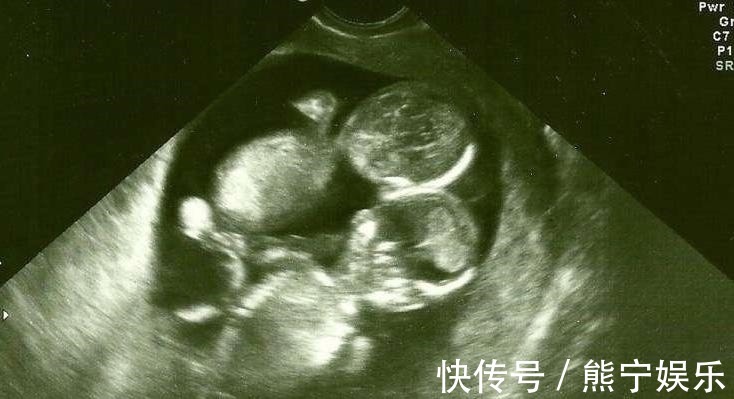

怀孕的妈妈都希望自己的婴儿健康!假如妈妈们事先知道生产时可能发生意外,你猜猜她们会不会生下来?有一位陈姓母亲,在照超音波时,知道了肚子里的双胞胎竟然是连体婴!她面临了很艰难的选择,看下去!陈女太久没有来月经,就去医院检查,医生说:「你怀孕了,而且是双胞胎!」可是医生接下来的话让她沉默了很久,她从医生口中,知道宝宝竟然是「连体婴」!她觉得晴天霹雳!

每次这位母亲的一想到自己宝宝是「连体婴」,就快哭了!虽然医生建议她进行人工流产,因为宝宝才4个月大,可是她仔细思考後,她决定留下婴儿的生命。7月的时候,她已经38周了、即将临盆,她有点不安,无法想像未来会怎麽样...

原本医生已经做好动手术的准备,没想到陈女生下了2个分别的个体,宝宝没有任何连体的迹象!医生非常惊讶!他很确定之前他在照超音波时,2个婴儿是连在一起的,後来医生猜测,可能当初他照射照音波时,2个宝宝紧紧抱住,才会误会!陈女掉下了放松的眼泪!她因为喜悦而流泪,她的勇气和母爱让人感动!分享给大家看看。图片来源于网络